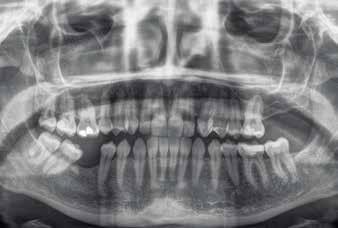

Figure 1. Initial X-ray of the case, where we can see in the second quadrant an edentulous section corresponding to tooth 27 that will be rehabilitated using dental implants.

Figure 2. Planning of the implant to be placed.

Figure 3. Post-surgical panoramic X-ray with the recently placed implant.

Figure 2 Figure 3 Figure 4 Figure 1